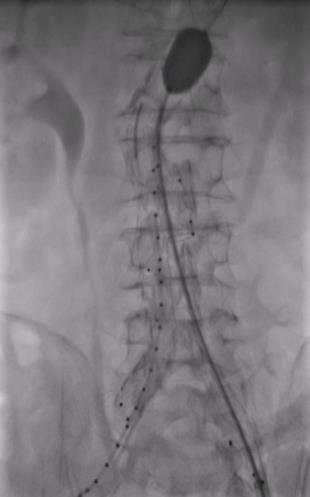

图1 预埋单弯型血管造影导管留置于主动脉腔内(肾动脉平面以上)Fig.1 A pre-positioned single-curve angiographic catheter placed within the aortic lumen (above the level of the renal arteries)